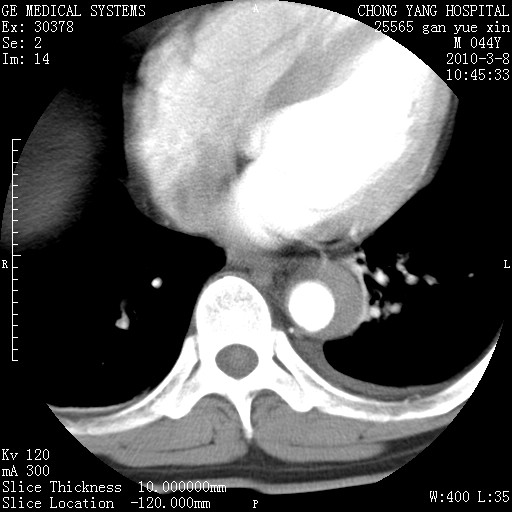

标题: CT24940:主动脉增强,典型病例。 [打印本页]

标题: CT24940:主动脉增强,典型病例。

夹层动脉瘤。

动脉夹层

夹层动脉瘤,典型

主动脉夹层。

动脉夹层的分型:

⒈debakey分型:根据主动脉夹层累及部位,分为三型:ⅰ型:原发破口位于升主动脉或主动脉弓部,夹层累及升主动脉、主动脉弓部、胸主动脉、腹主动脉大部或全部,少数可累及髂动脉。ⅱ型:原发破口位于升主动脉,夹层累及升主动脉,少数可累及部分主动脉弓。ⅲ型:原发破口位于左锁骨下动脉开口远端,根据夹层累及范围又分为ⅲa,ⅲb。ⅲa型:夹层累及胸主动脉。ⅲb型:夹层累及升主动脉、腹主动脉大部或全部。少数可累及髂动脉。

⒉stanford分型:a型:夹层累及升主动脉,无论远端范围如何。b型:夹层累及左锁骨下动脉开口以远的降主动脉。

夹层动脉瘤,少量胸水

夹层动脉瘤;左侧少量胸腔积液。

典型主动脉夹层。